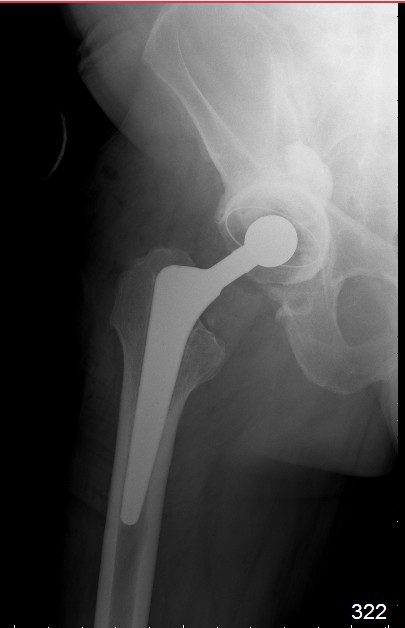

В конце 2008 года отметил боли в правой паховой области при опоре на правую ногу. На рентген снимках таза с тазобедренными суставами явных признаков нестабильности вертлужного компонента не обнаружено. В 2009 году нейрохирурги его "успешно" прооперировали на L\3-\4 связывая болевой синдром в правой паховой области с наличием грыжи указанного межпозвонкового диска. Состояние только ухудшилось, больной уже не мог долго сидеть, боль прогрессировала . Его в 2009 и 2010 годах смотрел ортопед, делались рентгенснимки, но почему то приходили к выводу что эндопротез справа стабилен. В марте 2011 года я впервые увидел его, через одну неделю после этого был прооперирован. На операции вертлужный компонент при упоре на него инструментом прокручивался во впадине и без труда был извлечен.

далее снимок у меня на приеме

при этом, у этого пациента была СОЭ 20 мм в час, лейкоциты и формула лейкоцитарная в норме. Можно было пунктировать сустав, но мы этого не сделали и оказались правы: при вскрытии сустава на операции, сустав был сухой и жидкость для посева мы бы не получили.

Но все же, мы провели его лечение как инфицированного, учитывая анамнез: нагноение операционной раны грудины, после операции на сердце. К тому, боли в правом тазобедренном суставе он отметил после осложненной операции на сердце.